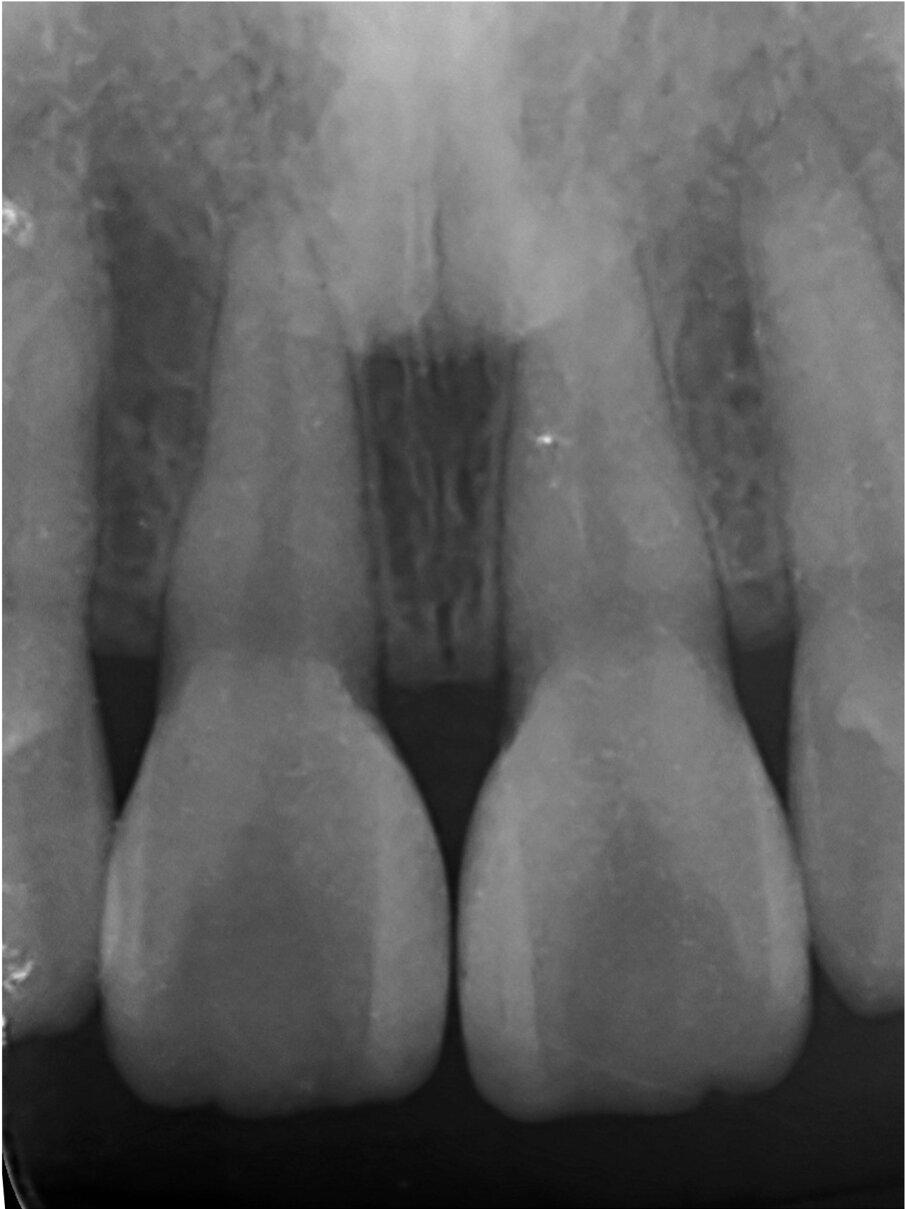

I did not have a favorite, but a less detested one, the hybrid technique, where after building the palatal wall with a wax-up, and then reinforcing the cervical area freehand, it was possible to execute the rest of the restoration with the matrix (Fig 1.). Although it was somehow efficient in my hands, it was complex.

Fig. 1: Common troubles with wax-up based techniques, the apical part of the palatal wall is defective.

What were the associated problems with the older techniques including the one you used? The greatest problem for the freehand techniques, without a doubt, is the lack of cervical precision and the creation of overhangs. I have seen countless patients with bleeding gums that are not able to floss properly. Another common problem with the classical approach was the final shape. With a double emergence profile, it gave the final restoration an awkward shape (Figs. 2–4). Problems for direct diastema closure exclusively with matrices are the over contouring and the under contouring at the cervical level, discordant contact points, shifted proximal contacts, and massive excess production. To be honest, I have always been discouraged from trying that approach.